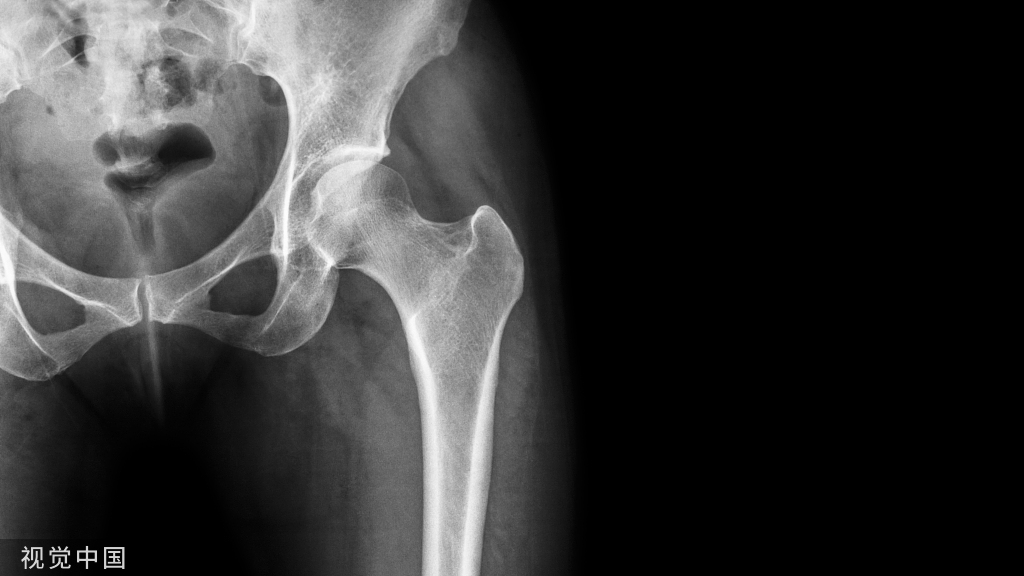

影像学检查中,DR、CT、MRI对于髌骨脱位来说都必不可少,不能相互代替。

DR检查包括下肢全长正位片、侧位片、膝关节正侧位、髌骨切线位等,有助于评估膝关节力线及滑车的形态,髌骨高度、髌骨倾斜,关节病等信息。

CT检查相对于DR检查,其主要优势在于其不仅不受体位影响,还可以动态观察膝关节伸屈活动中的髌股相对位置,能够提供髌骨不稳的准确信息,克服轴位X线片的不足,而且为了克服单层CT扫描中选点造成的测量误差,还可以使用图像叠加技术用于测量髌股关节排列关系,提高诊断率。

MRI检查是最常用的评估髌股关节软组织和滑车软骨的检查,在发现MPFL损伤时具有较高的敏感性和准确性,其特征性表现包括X线不能发现的软骨损伤及髌骨内侧面和股骨外侧髁的骨挫伤。MRI也可用于评估髌骨滑车指,测量髌骨高度等。